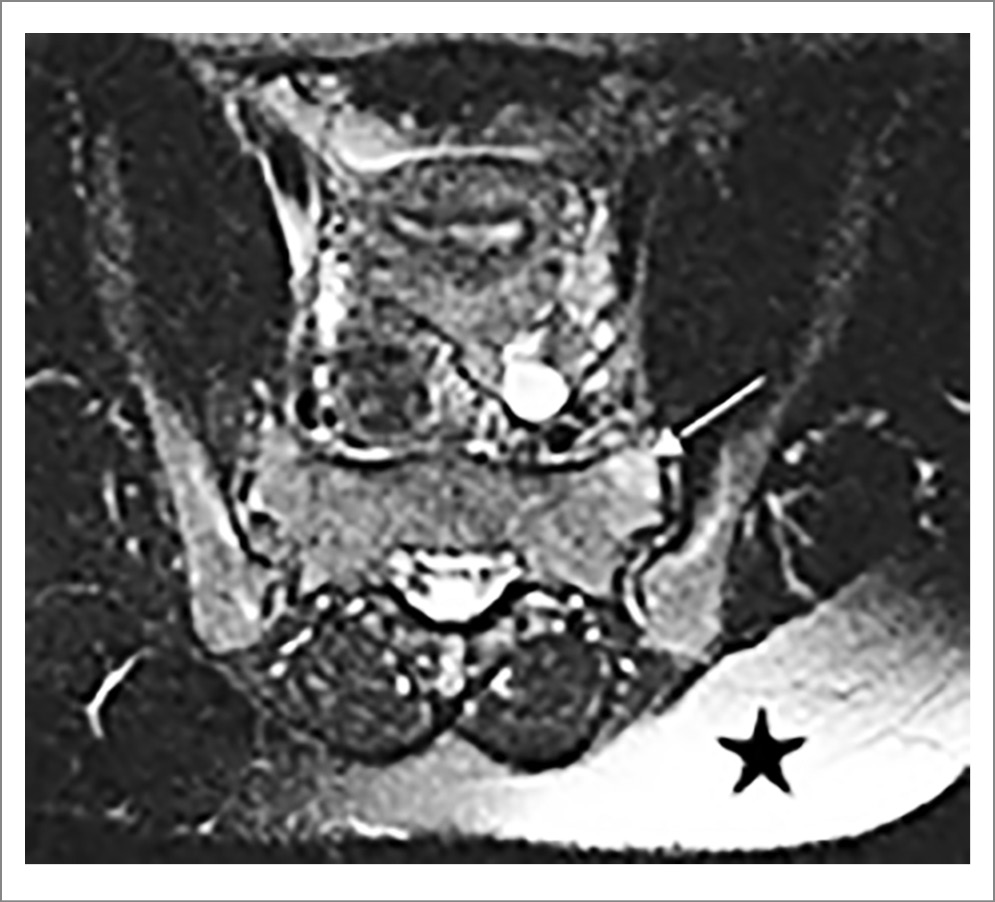

Рис. 12. МРТ КПС (в аксиальной проекции, режим Т2 FatSat): недостаточное жироподавление, о чем свидетельствует сохранение гиперинтенсивного сигнала от жировой ткани в правой ягодичной области (указано звездочкой). Участок гиперинтенсивного сигнала в правой боковой массе крестца имитирует отек костного мозга (указан стрелкой).